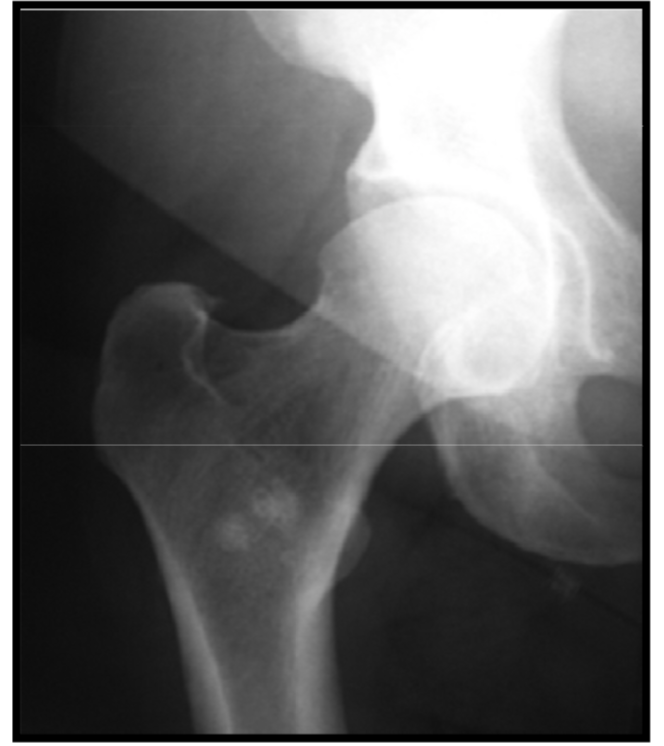

Developmental dysplasia of the hip

déformation